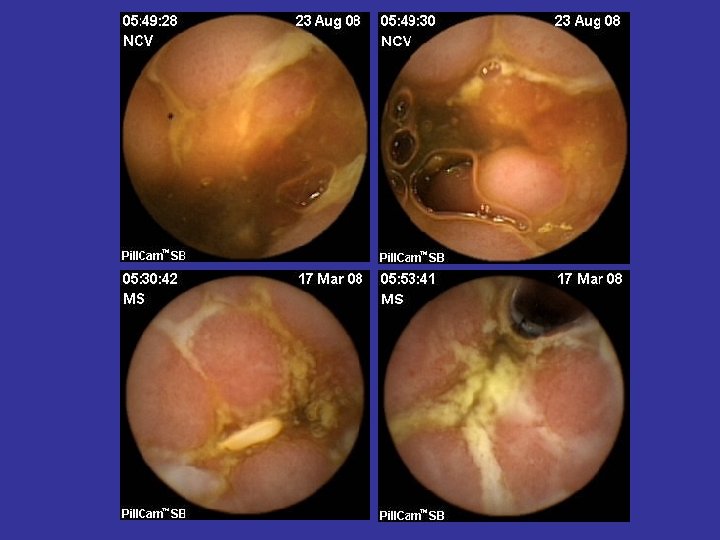

Hemoragia digestiva de cauza obscura (OGIB) • Indicatia majora a WCE • Acuratete diagnostica superioara (~ dubla) tuturor celorlalte metode diagnostice (Rx, PE, DBE, etc) • Administrare cat mai precoce dupa episodul hemoragic (< 48 ore) • WCE: rol in orientarea managementului si ameliorarea prognosticului • Repetarea WCE dupa un examen negativ creste acuratetea diagnostica

Tipuri de leziuni depistate in BC • • Eroziuni Edem mucosal Congestie parcelara Ulceratii aftoide; Ulcere liniare/ neregulate/ confluente; Pseudopolipi inflamatori; Stenoze inflamatorii;